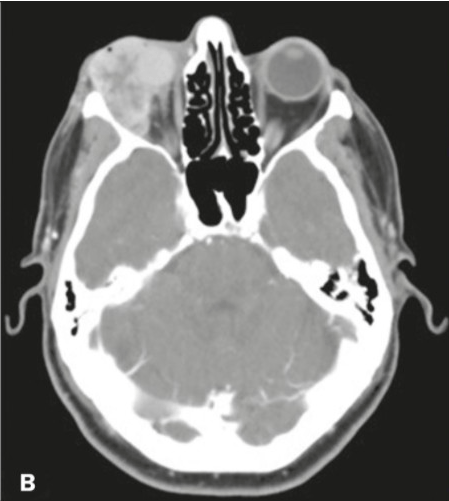

A tomografia computadorizada das órbitas é um exame de diagnóstico por imagem de alta qualidade, que permite a avaliação desta região de maneira anatômica, sendo ela um exame que serve não só para auxiliar o médico no estudo de diversas patologias (doenças) como também para avaliar as respostas aos tratamentos. Em algumas situações, é solicitado o uso de contraste iodado – via endovenosa –, para uma visualização mais detalhada da área desejada.

A órbita é uma cavidade do esqueleto da face onde se “encaixa o olho”. Anatomicamente tem uma forma de pirâmide, permitindo acomodar o bulbo do olho, os músculos que permitem a movimentação do olho, os nervos, os vasos sanguíneos e o aparelho lacrimal (para a produção de lágrimas).

Por meio da tomografia de órbita com uso de contraste, são analisadas as estruturas vasculares da região estudada. A solução de contraste iodado é administrada por via endovenosa e distribui o contraste entre as estruturas com fluxos sanguíneos, realçando as estruturas hipervascularizadas, mostrando, por exemplo, tumores ou processos inflamatórios.